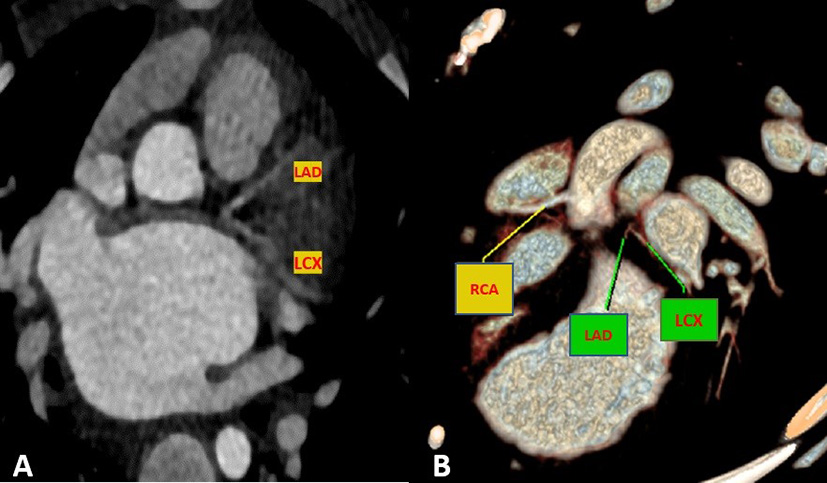

Cardiac magnetic resonance was performed to investigate the possible underlying pathology, which confirmed severe LV dilation, severely reduced systolic function (LVEF: 22%), and severe MR (Figure 2). Late gadolinium enhancement (LGE) sequence demonstrated subendocardial to transmural scar in the basal and especially at the mid anterior and anteroseptal segments, raising suspicion of an ischemic insult. Gated CT coronary angiography (Figure 3) demonstrated an absent LM stem with a centripetal filling of the small caliber confluent LAD and circumflex, likely from collaterals from a dilated right coronary artery. Angiography confirmed the LM atresia with a retrograde collateral filling of LAD and LCX arteries from a dominant RCA. There was no connection to the pulmonary arterial branches (Figure 4; Supplementary Videos 1, 2). Considering the extent of myocardial fibrosis, small-sized coronary arteries and LV remodeling were required, and according to the decision of heart team specialists, the patient underwent medical treatment for heart failure and was scheduled for a heart transplant.

Figure 3

Maximum intensity projection (A) and volume rendered (B) CT images demonstrate an absence of the LM artery with proximally connected left anterior descending artery (LAD) and left circumflex artery (LCX).